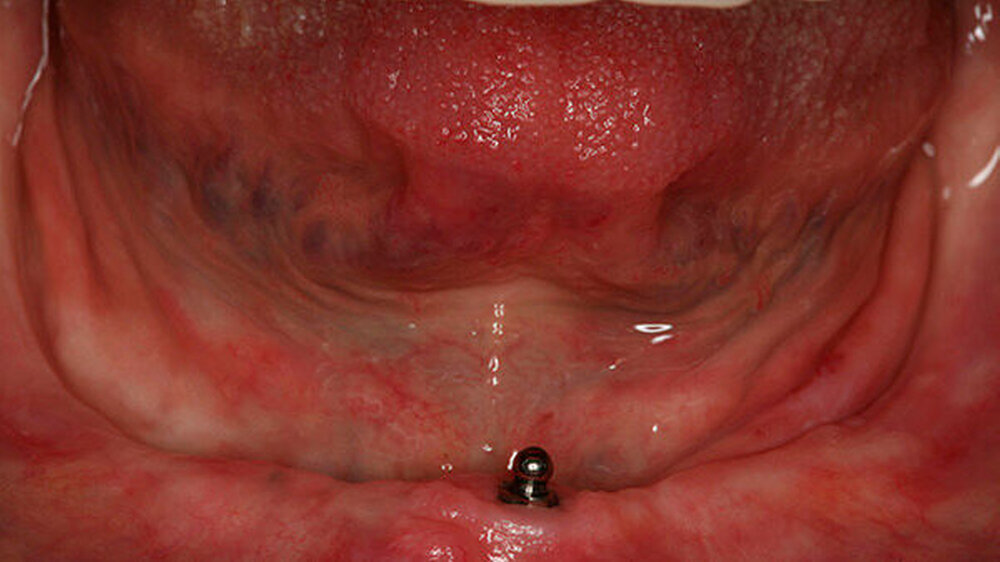

Beispiele für individuellen ZE

Die Jahrestagung der Deutschen Gesellschaft für Prothetische Zahnmedizin und Biomaterialien (PGPro) in Ulm geht der Frage nach, welche Versorgungskonzepte - mit guten Langzeitergebnissen - individuell und preiswert machbar sind. Gute Beispiele finden Sie in unserer Bilderstrecke!